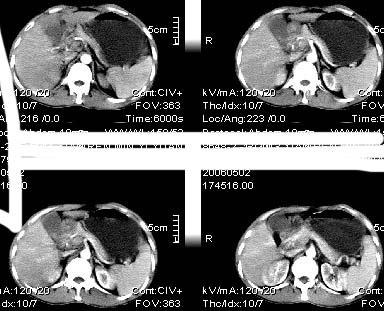

男:42岁。反复恶心呕吐半年。b超:右肝内多发占位,胆石胆囊炎.胆总管扩张

本例特点动脉期右叶近肝门区可见高密度强化,后段也见早期强化,静脉期肝门区高密度区造影剂退出,余密度均匀,考虑肝癌伴动静脉漏,肝右叶上段可见扩张胆管,考虑由于肿瘤压迫胆管引起阻塞,

鉴别 胆管细胞性肝癌,无动脉期强化,